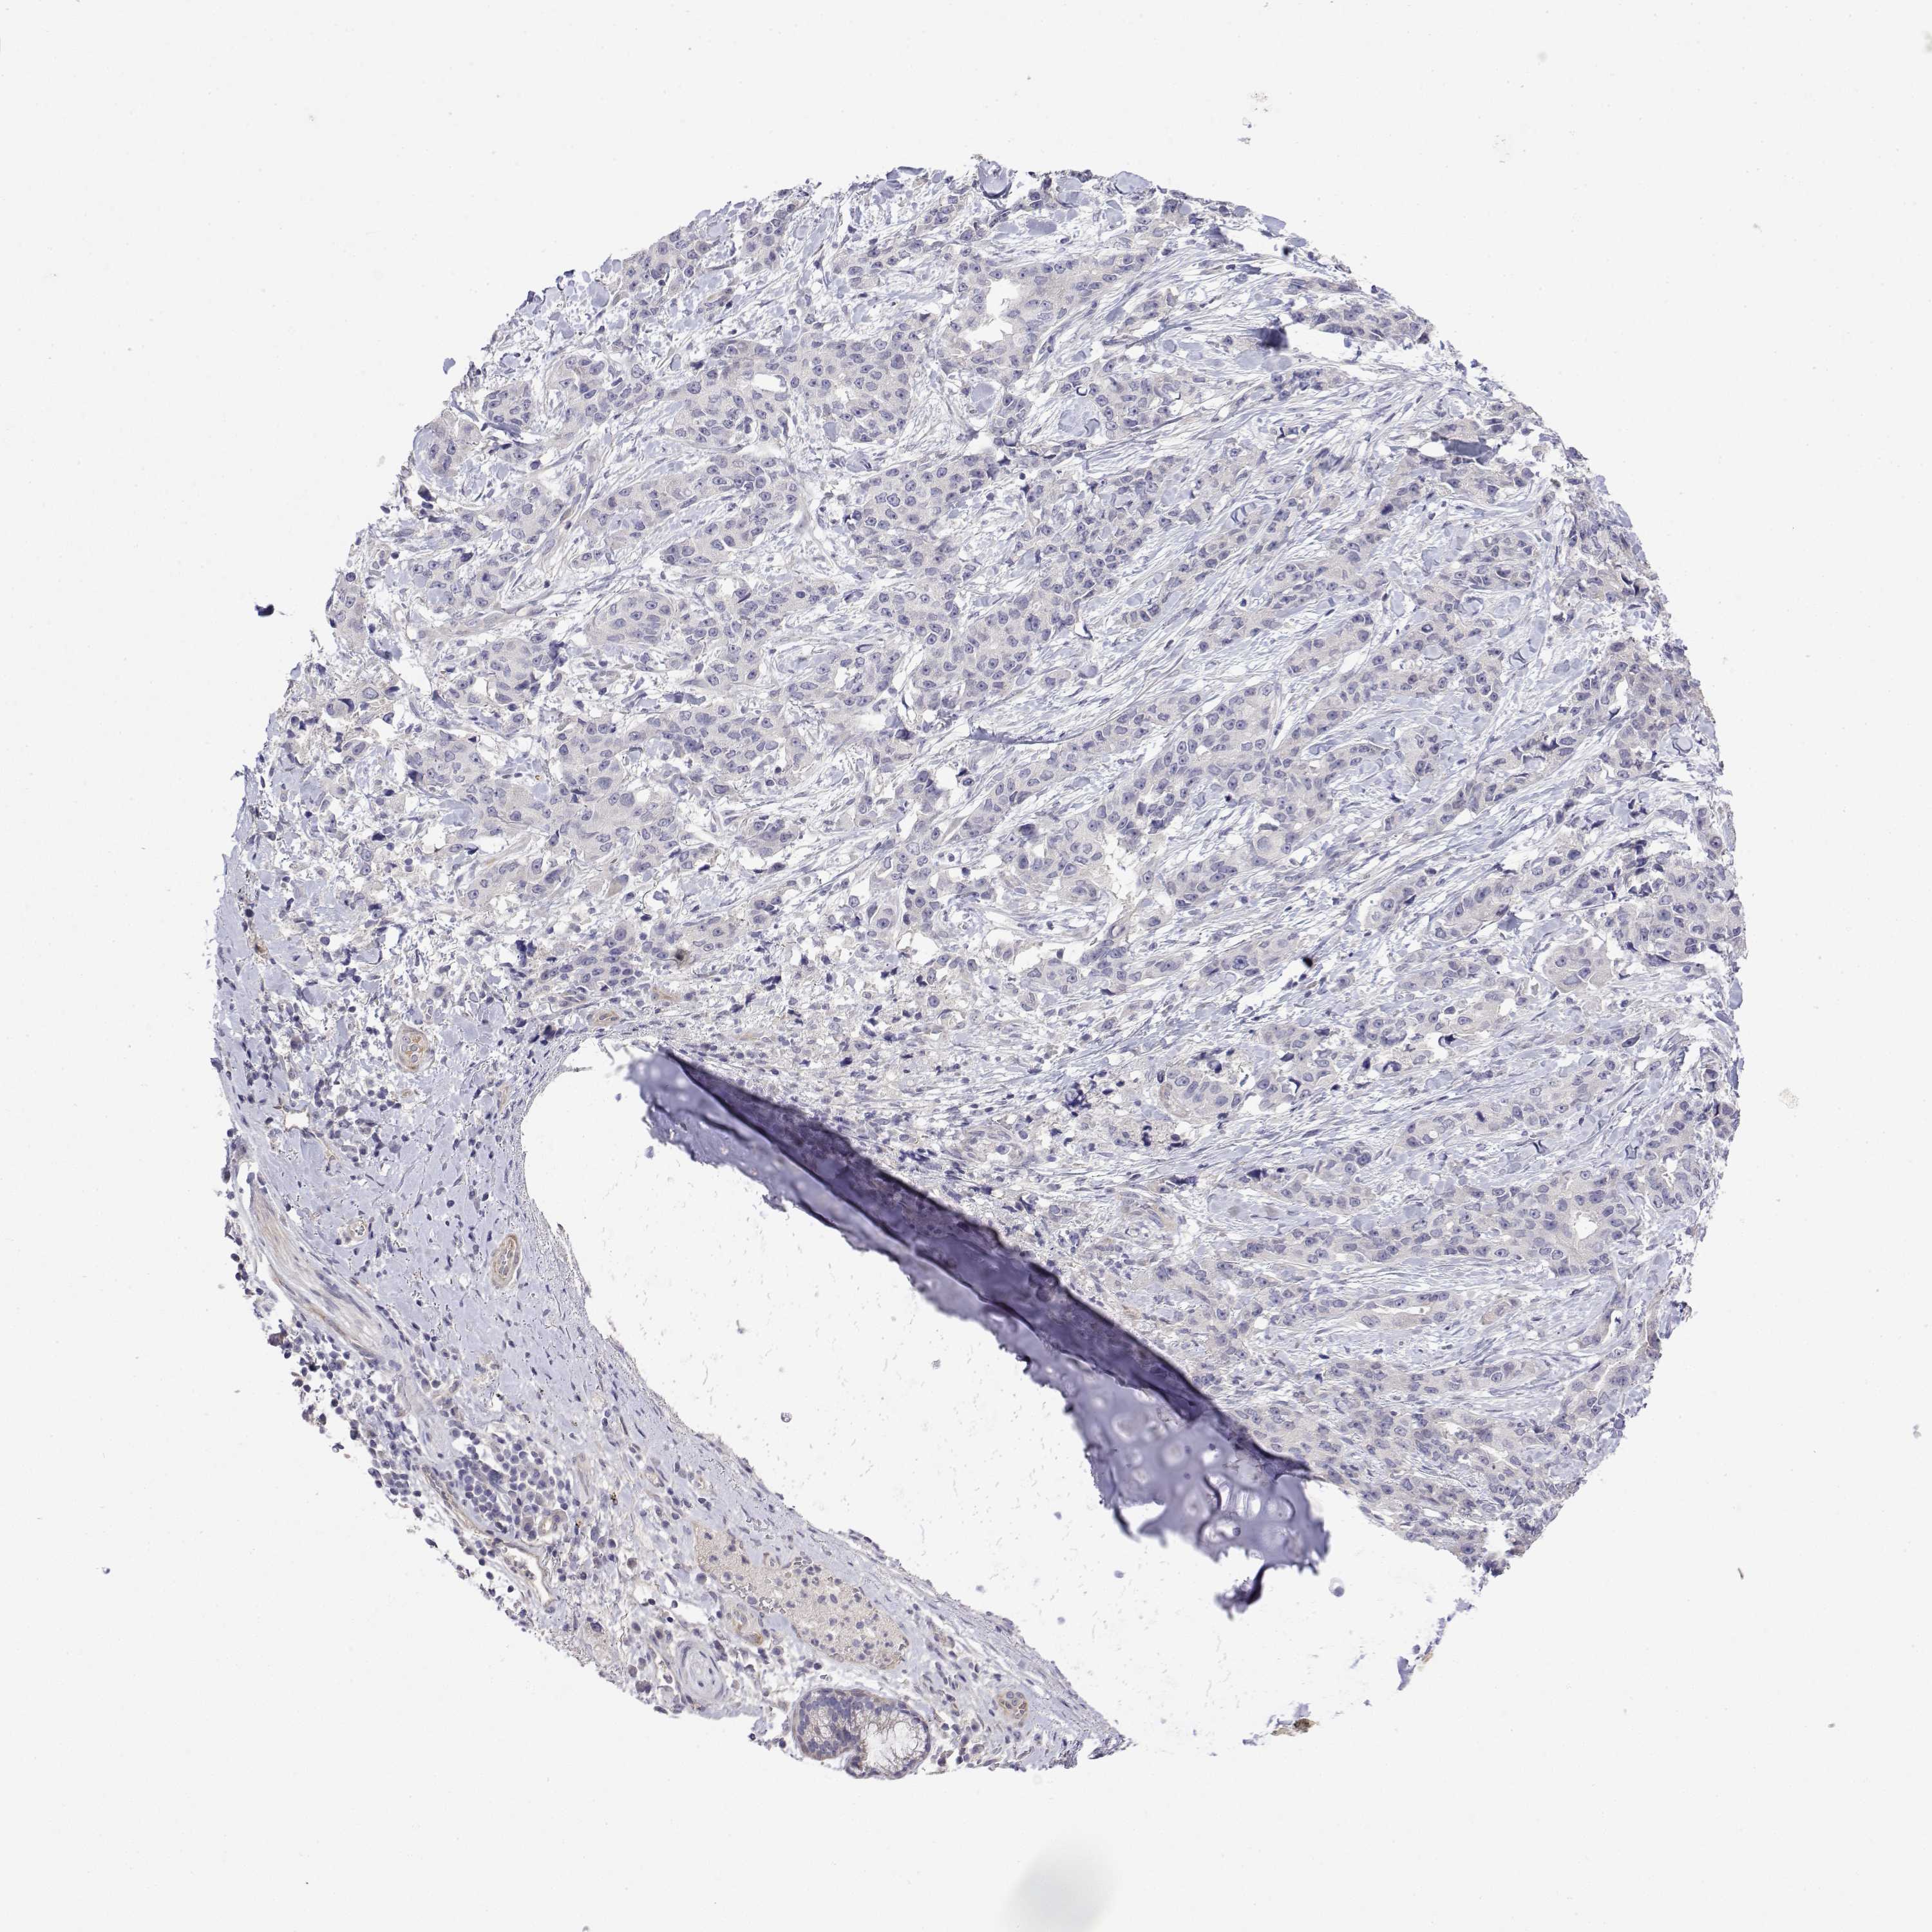

CANCER LUNG CANCER Show tissue menu

Lung cancer

Human cancer